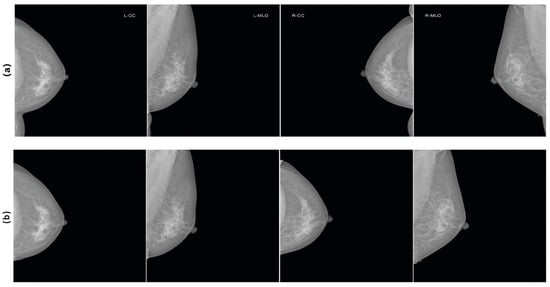

All images were standardized, displaying only the mammograms without projection information. Thus, we created a dataset consisting of mammographic images where all glands are oriented in the same direction and projection labels have been removed. An example of images after applying the mask and rotation is shown in Figure 2.

Figure 2.

An example of images from the same patient: (a) before applying the mask and rotation, (b) after applying the mask and rotation.

Each patient has four images: LCC (left craniocaudal), LMLO (left mediolateral oblique), RCC (right craniocaudal), and RMLO (right mediolateral oblique). To prevent potential errors in identification, where the model might match images from different projections of the same patient, we took several important steps.

Firstly, all images from the right side (RCC and RMLO) were flipped along the vertical axis to align with the projections from the left side (LCC and LMLO). This unification of image orientation prevents the model from being biased based on the gland’s projection.

Secondly, we applied binary gland masks as in [46] to remove projection labels from the images. This ensures that the model does not rely on these labels for identification and focuses exclusively on mammographic data.